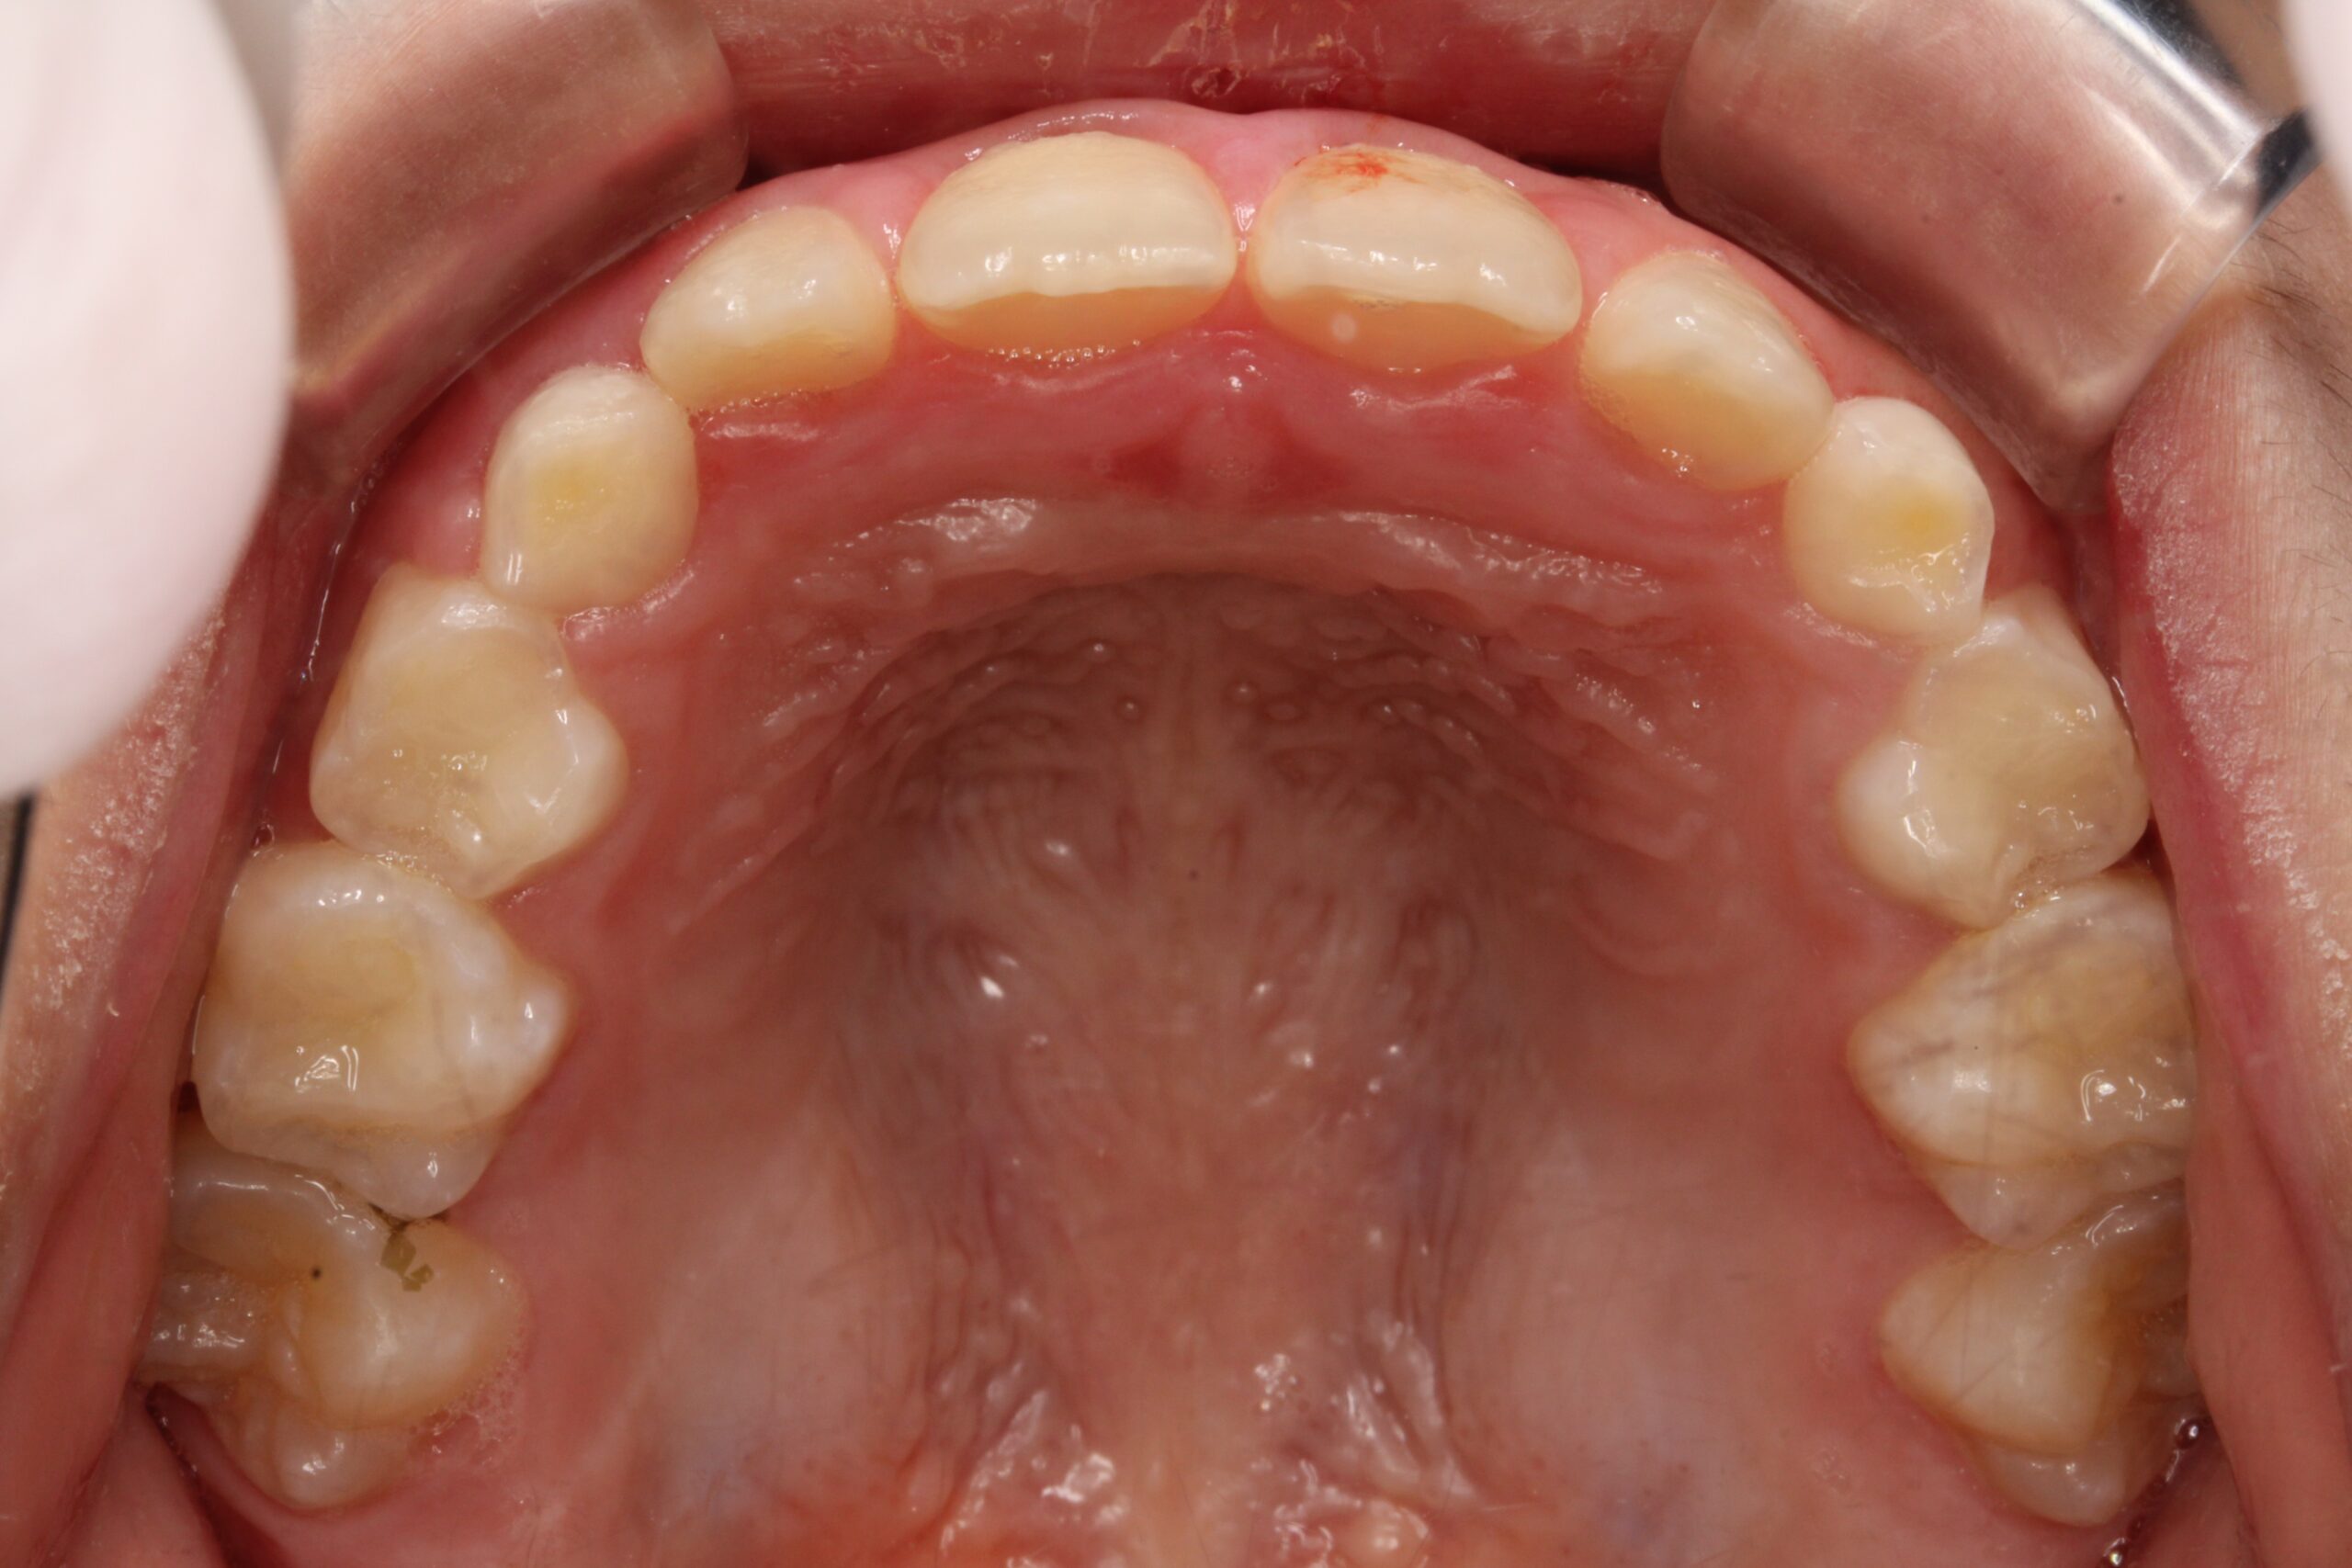

矯正術前:下顎

| 主訴 | 下の前歯のがたつきが気になる |

| 治療期間 | ・拡大床矯正:15カ月 |

| 治療内容 | 患者様は、下の前歯のがたつきを気にされており、矯正検査後叢生Ⅰ級と診断いたしました |